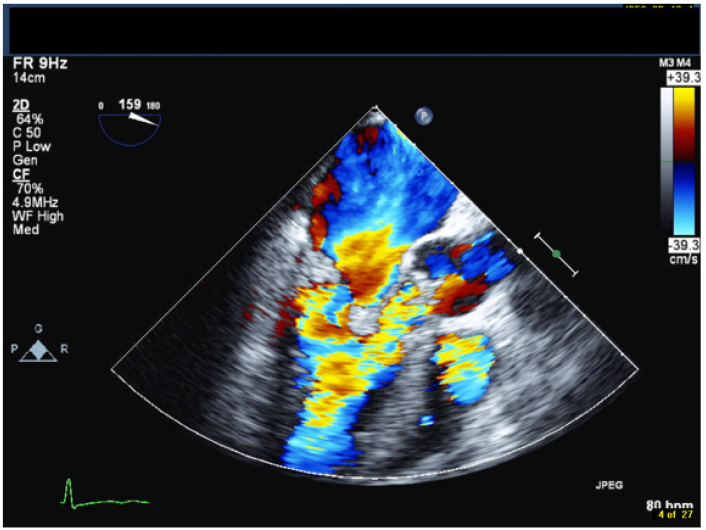

A 42-year-old male with a history of chronic nephrolithiasis presented to the hospital after neighbors found him unconscious at home. On initial evaluation, he was febrile (38.9) with blood pressure of 120/104mmHg. He was severely hypoxic with a sinus rate of 90 beats/minute. His examination revealed multiple abrasions, and he was minimally responsive with a holosystolic murmur at the apex. His electrocardiogram showed normal sinus rhythm with no acute ST-T wave changes. Laboratory data revealed a white cell count of 17.4/nl, platelet count of 109/nl, lactate level of 4.8 mmol/l and creatinine of 1.57mg/dl. Computed tomography of the head revealed multiple regions of acute infarction involving the right inferior cerebellum, left occipital lobe with mass effect on the left occipital horn. He underwent a transthoracic echocardiogram that showed vegetations on both the mitral and aortic valve. He underwent a trans-esophageal echocardiogram, which demonstrated multiple vegetations on the mitral (Figure 1), aortic (Figure 2) and pulmonic valves (Figure 3) with severe pulmonic, mitral and aortic insufficiency (Figure 4 & 5). Despite negative urine cultures, serial blood cultures grew Aerococcus urinae and he was given appropriate IV antibiotics. He was evaluated for possible valvular surgery and was deemed to be a poor surgical candidate. He later developed splenic and renal infarcts followed by significant hemodynamic instability requiring vasopressors and ultimately succumbed to his illness after he developed multi organ failure and disseminated intravascular coagulation.